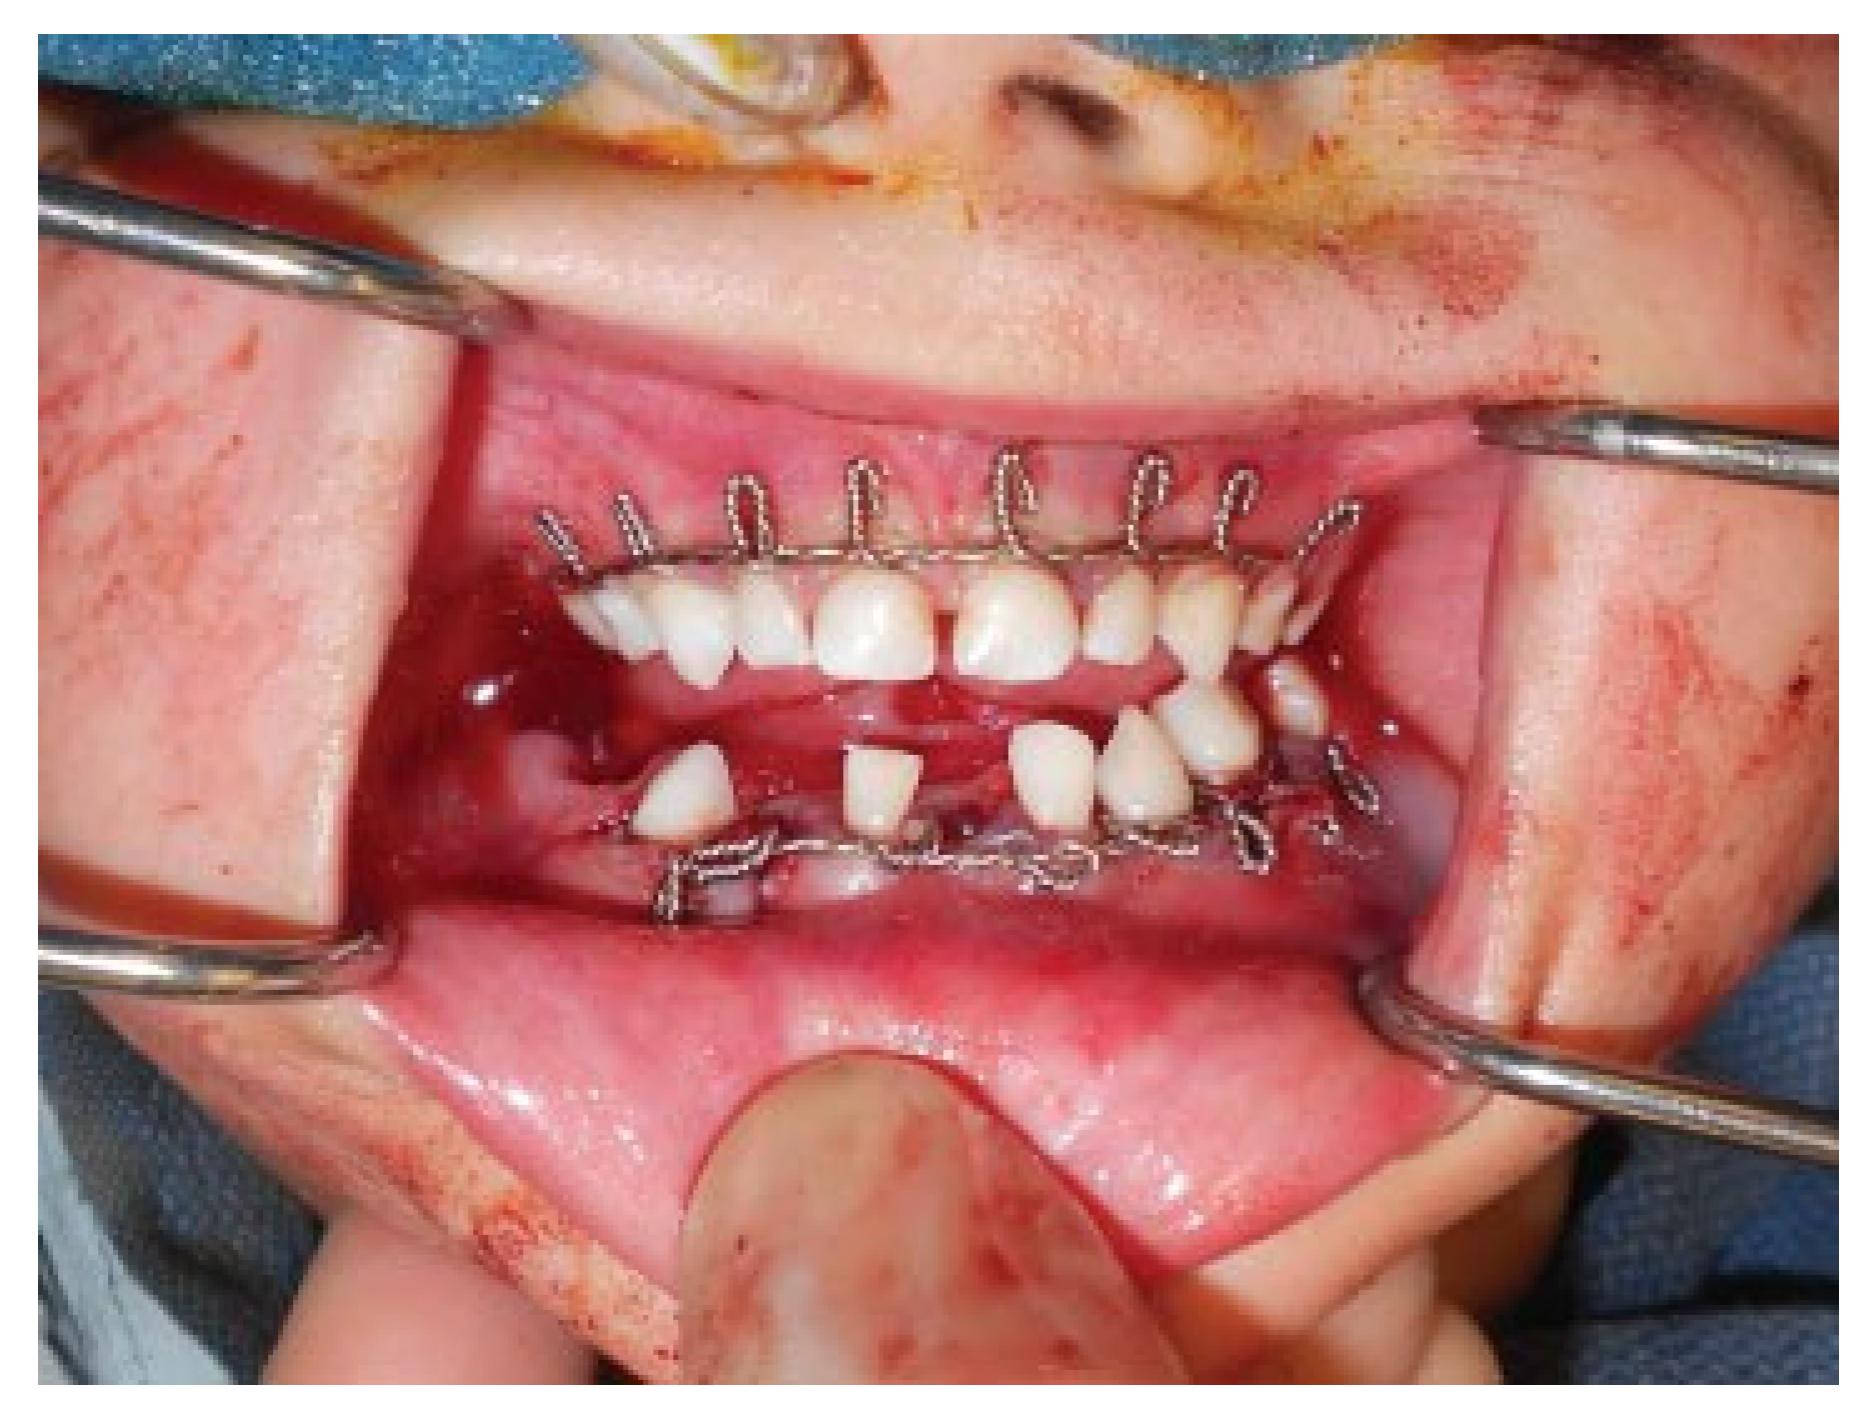

Modifications to this procedure include using 24-gauge stainless steel wire that is passed from the last molar as originally described (Figure 2). The wire is then twisted from one side of the dental arch to the other (Figure 3). Ideally, circumdental ligatures are passed to secure the individual teeth as the cable is being twisted (Figure 4). This will allow for secure fastening of the cable and ligature complex. Finally, when the wires composing the Risdon cable have reached the contralateral molar tooth, it is then secured and the final circumdental ligature is placed. The circumdental wires are cut and twisted in a traditional fashion that will allow loops for securing elastics or wiring to establish MMF or guiding functions (Figure 5). If elastics are used for MMF, it is most unusual for the Risdon wiring to pull off or otherwise fail as the elastics “give.” Aside from establishing MMF, this procedure may also be used for splinting avulsed or luxated teeth, and may be supplemented with autopolymerizing resin for stability (Figure 6). Following application of the Risdon cable, open reduction internal fixation may then be performed with the patient in MMF (Figure 7).

Figure 5. Final wiring of both the maxilla and mandible.